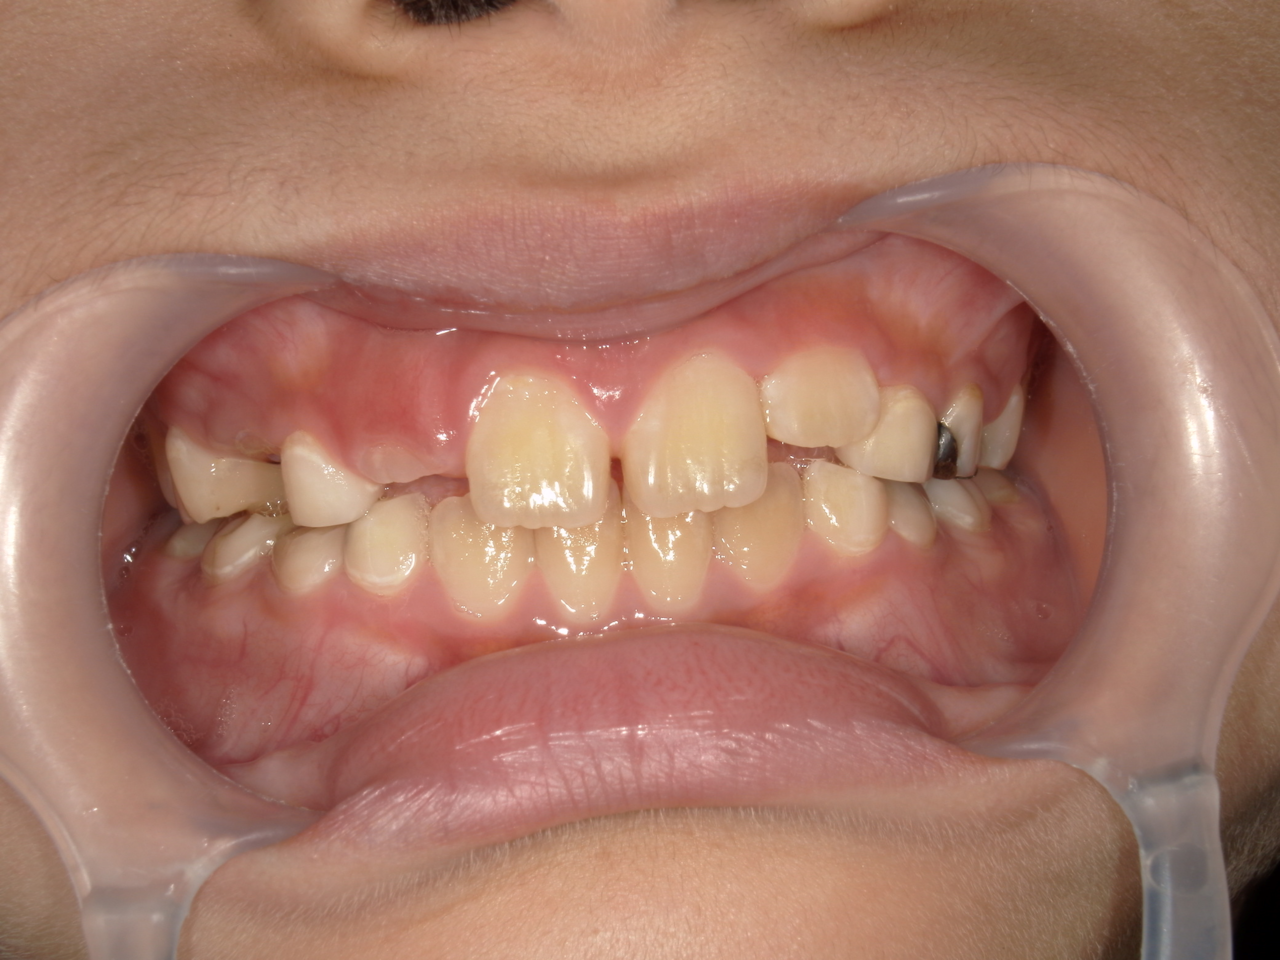

治療前

治療説明 歯科矯正で取り外し可能な矯正方法である床矯正で治療しました

治療期間 4年

治療費用200000 円

治療の副作用(リスク)歯の動き方には個人差があり、予想された治療期間が延長する可能性があります。。床矯正の使用状況、矯正歯科治療には患者さんの協力が必要であり、それらが治療結果や治療期間に影響します。2次矯正が必要になる場合もあります。